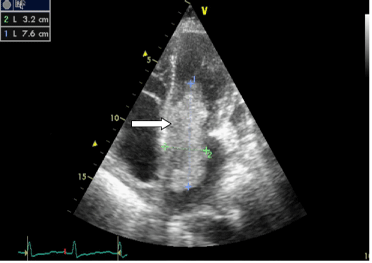

Mitral Valve Obstruction and Pulmonary Hypertension Caused by a Giant Left Atrial Myxoma Prolapsing in the Left Ventricle

Atrial myxomas are the most common primary cardiac tumors to diagnose. They are benign and have variable presentation. They have an excellent prognosis following surgical excision. We report a case of a 60 year old female who presented with initial signs of both right and left heart failure, fever and cough. Auscultation of the heart revealed an apical mid diastolic murmur. Trans-thoracic and trans-esophageal echocardiography revealed a pedunculated, giant left atrial myxoma that prolapsed through the mitral valve into the left ventricle in diastole producing functional mitral valve stenosis. The patient underwent a successful surgical excision of the tumor. The diagnosis and management of atrial myxomas is here reviewed.